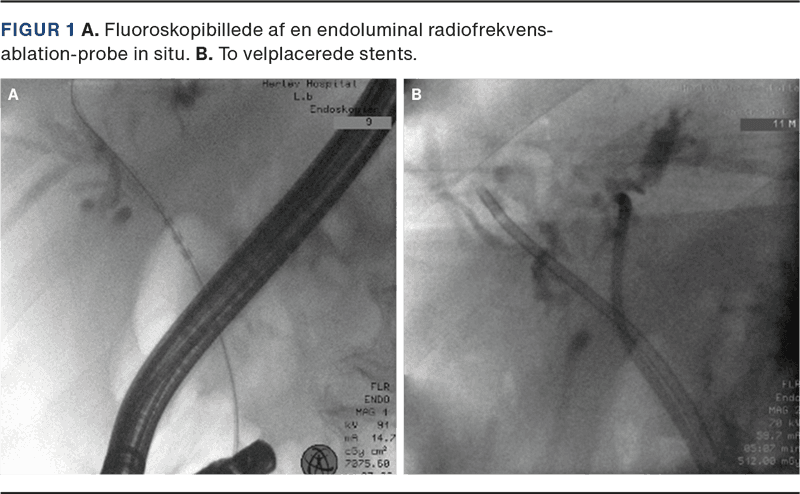

Der er i løbet af de sidste par år blevet udviklet dedikerede prober til endoluminal radiofrekvensablation (RFA) (Figur 1), som kan foretages i tillæg til ERCP mhp. cytoreduktion og forbedret drænage.

Endoluminal RFA består af induktion af lokal vævsnekrose ved kontrolleret RFA ved at lede højfrekvent strøm gennem en probe, hvilket medfører intermitterende opvarmning af vævet, således at temperaturen holdes nogenlunde konstant på 70-75 °C. Proceduren udføres i forbindelse med ERCP, og til endoluminal RFA benyttes en dedikeret probe (ELRA, Taewoong Medical, Los Angeles, USA) bestående af 2-4 små elektroder placeret med få millimeters afstand, som er synlige på fluoroskopi [4]. Proben indføres fluoroskopisk vejledt gennem tumorstenosen, og ablationen foretages typisk i 1-2 min med 7-10 W. Der findes flere prober med effekt i forskellig dybde og længde samt mulighed for indstillinger alt efter lokalisationen.